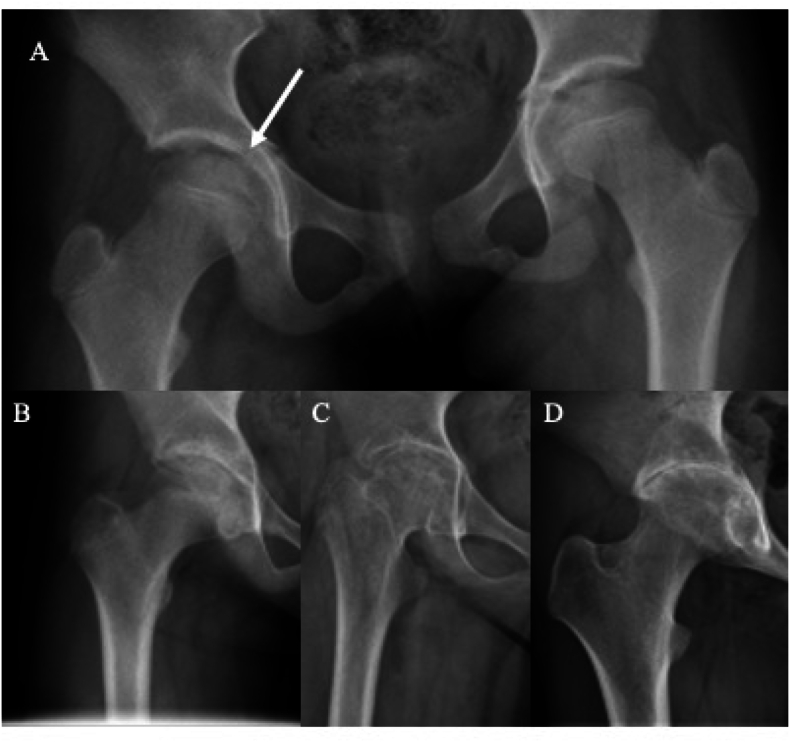

Idiopathic chondrolysis of the hip (ICH) is a rare condition characterized by the acute and rapidly progressive destruction of cartilage. ICH typically presents in peri-pubescent females with acutely worsening hip pain, a deterioration in range of motion (ROM), and distinctive imaging and biopsy findings. Variability in outcomes, ranging from complete resolution of symptoms to a permanently ankylosed hip, has been observed in both conservatively and aggressively treated cases. The treatments described often consider patient factors and disease stage yet consist of inconsistent combinations of pharmacologic and surgical approaches. Consequently, it is challenging to compare outcomes across different treatment methods. Although recent literature has enhanced our understanding of the epidemiology and natural history of ICH, a consensus on optimal management is still lacking, highlighting the need to investigate the components and outcomes of evolving treatments. Since the last systematic review of imaging findings and treatment regimens for ICH, over 50 new cases have been documented in the literature. However, limited data still exist regarding patient-reported outcomes. Our aim is to review and contribute to the current evidence guiding the management of ICH by analyzing data on presentation, clinical and radiologic findings, and treatment outcomes.